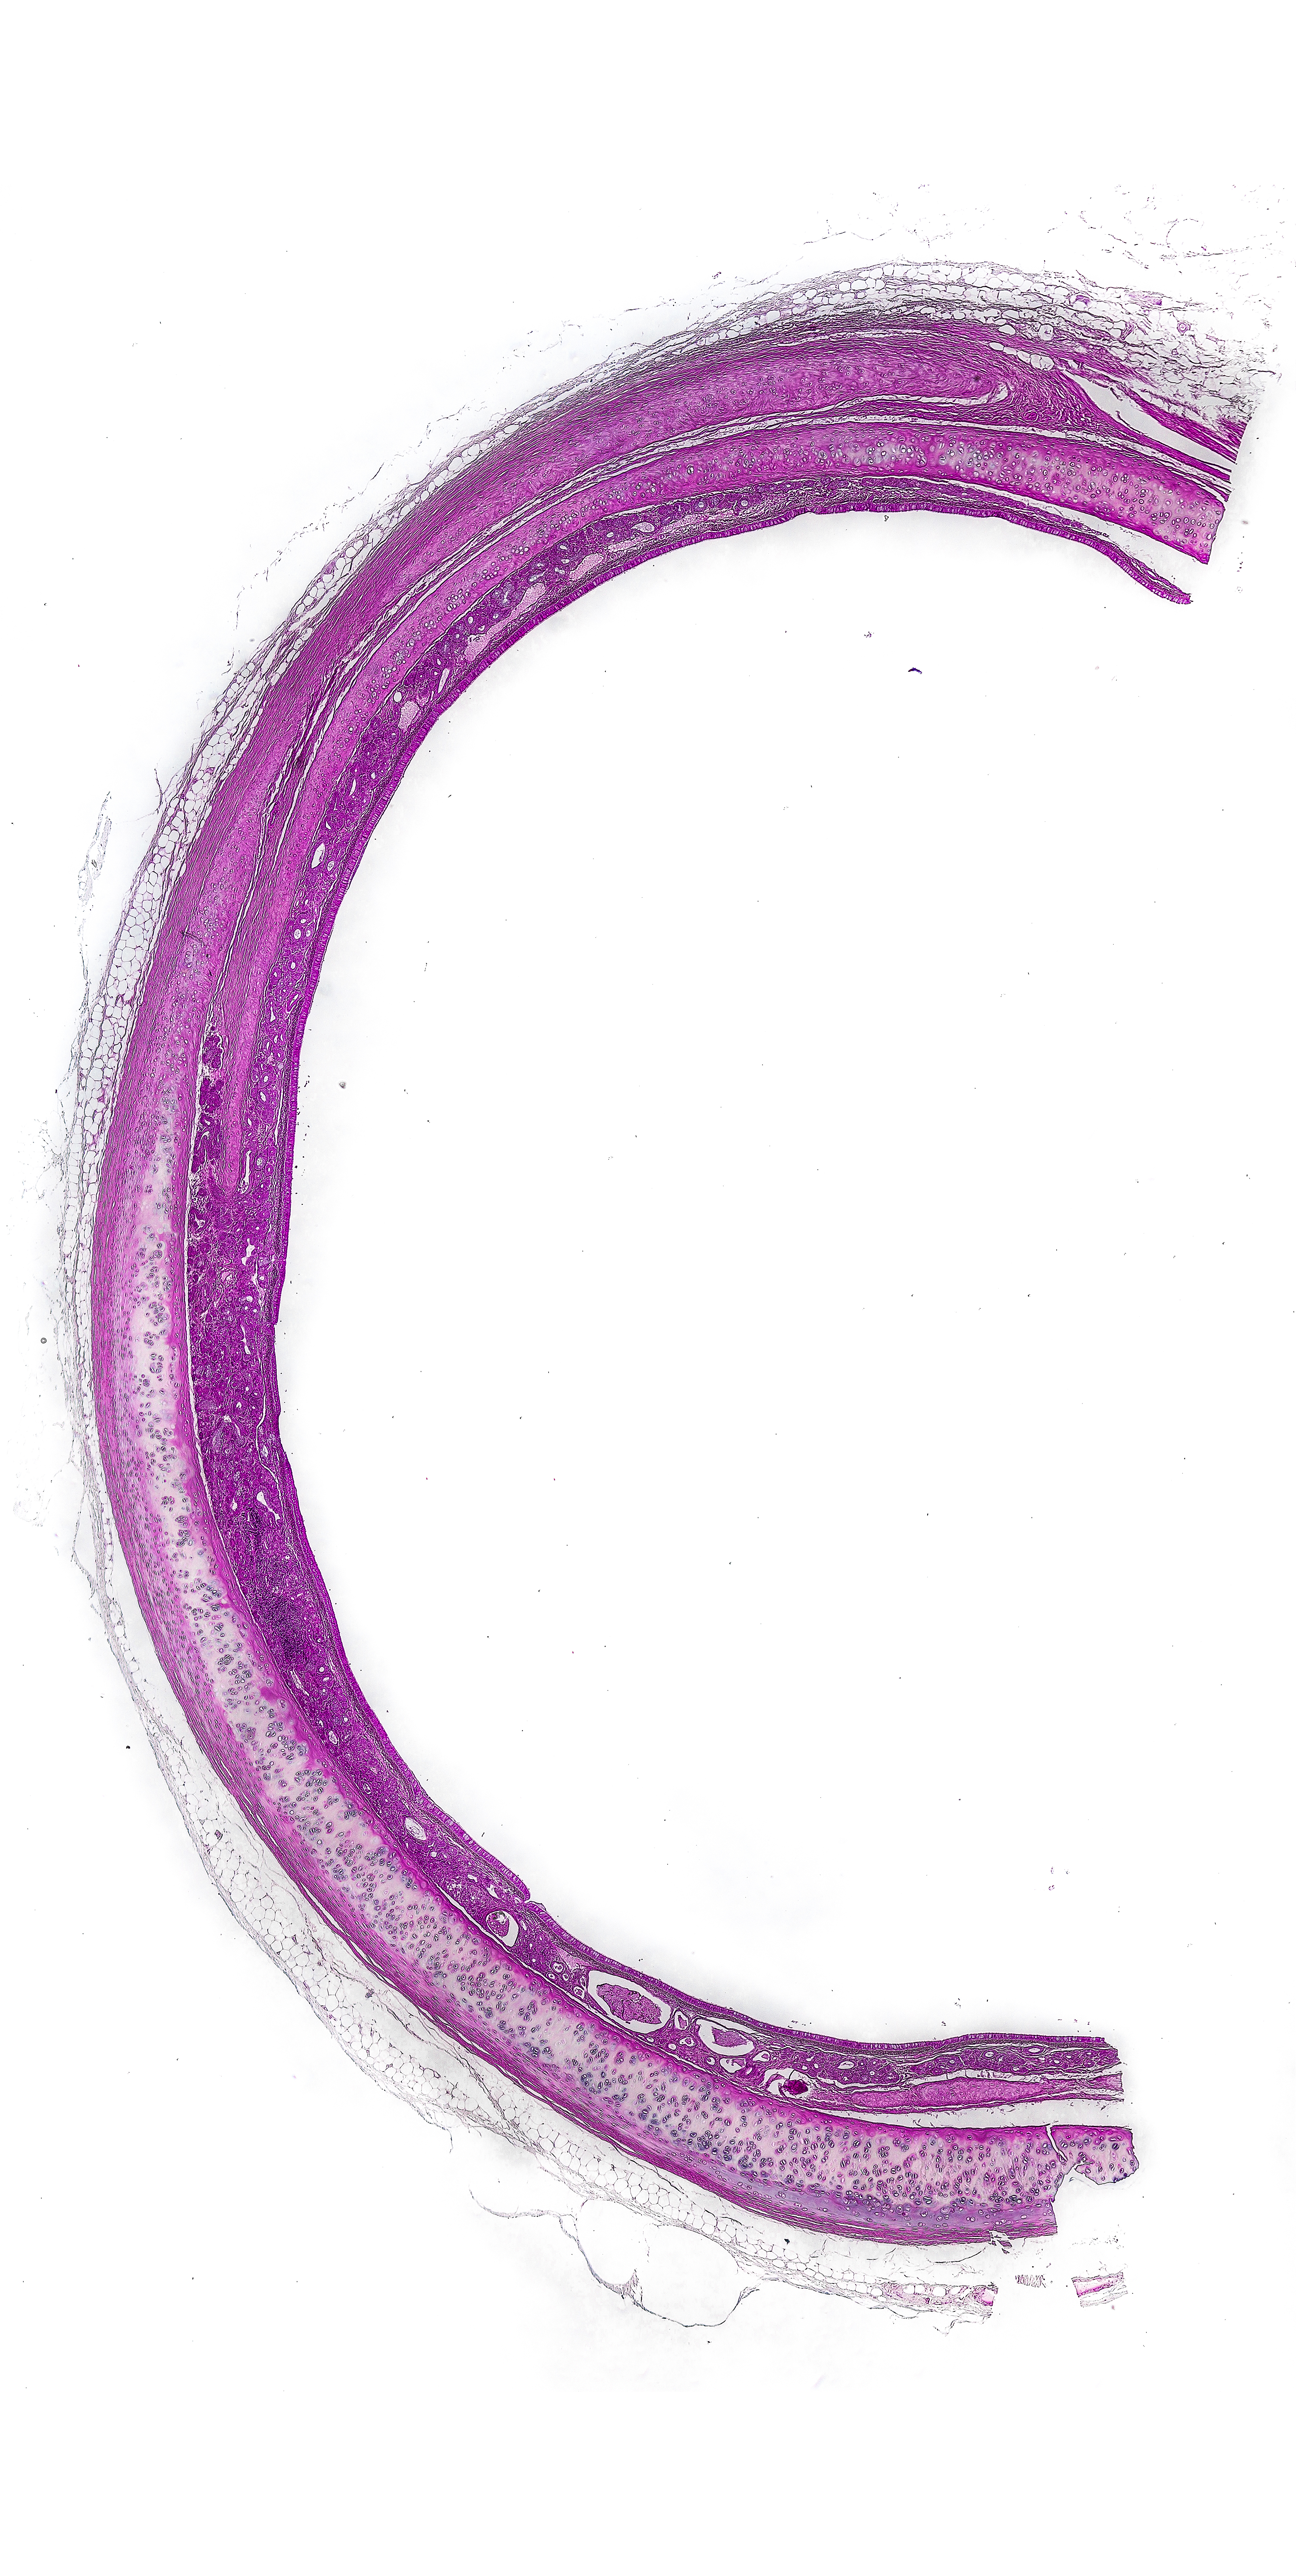

Digestive System

Stomach

1. Mucosa

Epithelium | simple columnar epithelium

Cellular component | surface lining cells, parietal cells, regenerative cells, mucous neck cells, chief cells, enteroendocrine cells, NO goblet cells

Lamina Propria | loose connective tissue, gastric glands (simple tubular)

Muscularis Mucosae | IC/OL SMC layer & third circular SMC layer

2. Submucosa

Connective Tissue | dense irregular collagenous connective tissue

3. Muscularis Externa

Inner oblique SMC

Middle circular SMC

OL SMC